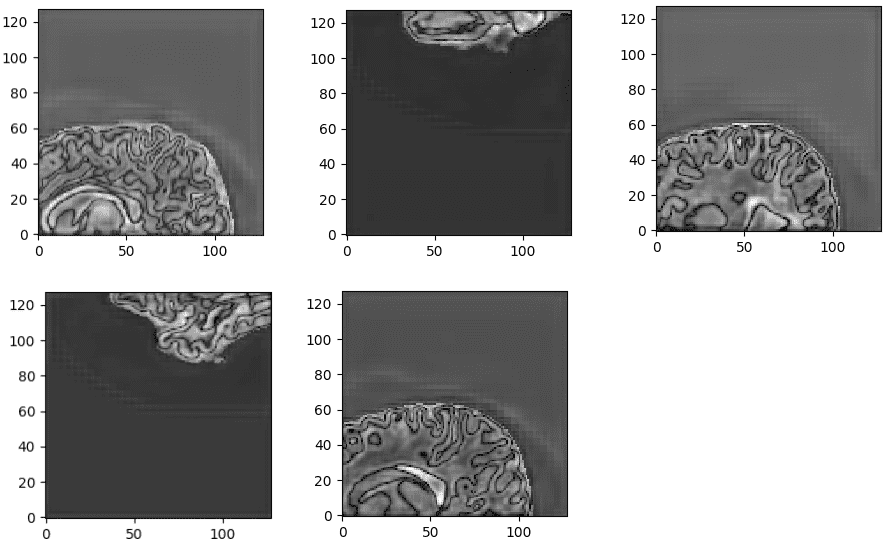

来自训练过的3D-Unet的未规范化的最后一层预激活。该网络学习高度语义的任务相关内容,对应于与输入相似的大脑结构。